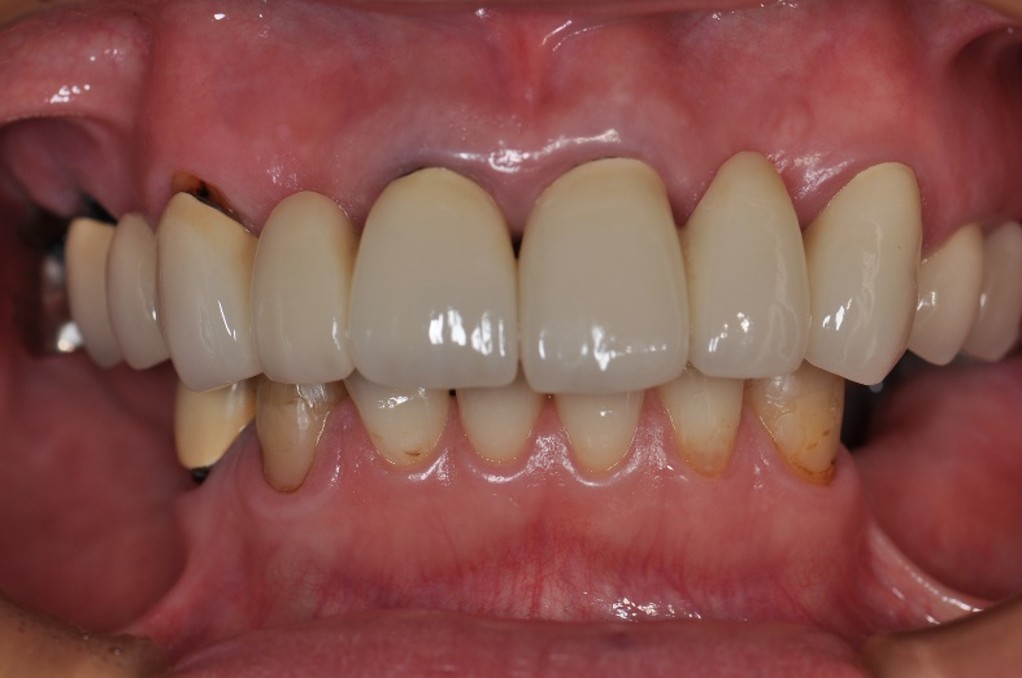

治療前

治療後